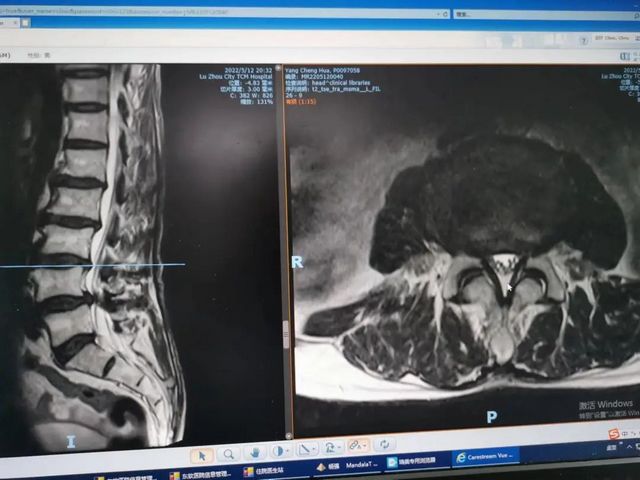

“双椎”同患病,巧手予治疗——看泸州市中医医院骨科大夫的手艺

半年前68岁老人杨先生的颈椎和腰部同时出现了疼痛,导致下地行走困难吃药缓解后,此病也反复发作,那这是什么病?又是怎么回事呢?原来,杨先生无明显诱因的出现颈肩部、腰部疼痛,在当地医院住院治疗后症状稍缓解,随后疼痛症状又加重,并反复发作。近日,...